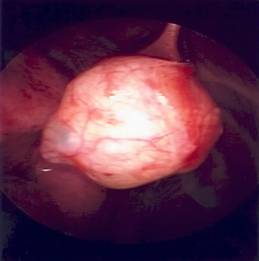

Figure-2:

Appearance on bronchoscopy

The

tumor was visualized after retracting the diaphragm inferiorly and the lung

superiorly. The tumor was tethered by a

narrow stalk, which was isolated and divided.

The specimen was sent to pathology.